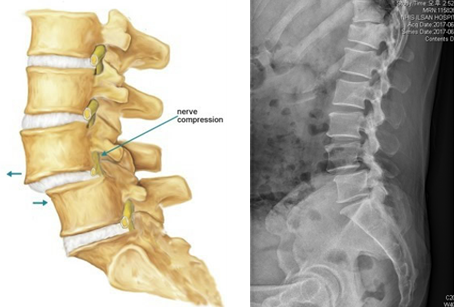

요것이 척추 전방전위증입니다. 영어로는 spondylolisthesis라고 합니다.

우선 위의 그림을 보시면, 화살표 된 부위의 척추가 앞쪽, 그림상으로는 왼쪽으로 삐져나온 것이 보일 겁니다. 앞쪽(전방)으로 척추가 이동(전위)했기 때문에 전방전위증이라고 부릅니다.

척추 전방전위증(spondylolisthesis)은 척추 분리증(Spondylolysis)이 선행됩니다.

그림에 보이는 부위가 퇴행성 변화 등으로 끊어지게 되고, 시간이 지나면 허리 척추뼈가 앞으로 밀려나게 됩니다.

자연히 신경의 압박, 협착이 동반될 수 있습니다.